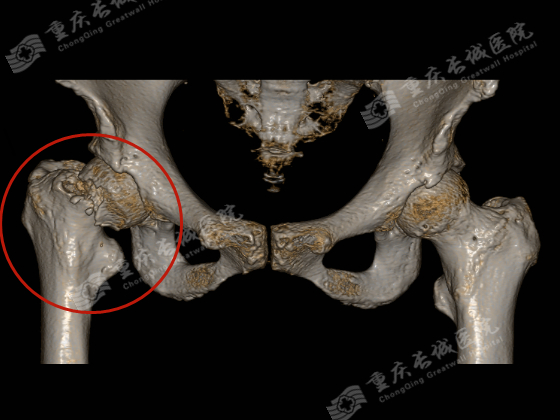

李嬢嬢就是属于此类情况,入院诊断为:右股骨颈骨折。

人工髋关节置换术是治疗股骨头坏死、髋关节发育不良、退变性髋骨关节炎、类风湿性关节炎等疾病终末期病变的最重要和最有效的手术之一。

人工股骨头置换创伤小、手术时间短、出血少、麻醉风险小,临床实用价值大。对于高龄、骨折前活动能力低、合并有多种疾病、全身情况较差的患者选择人工股骨头置换为佳。而双极人工股骨头在单极人工股骨头的基础上增加了一个摩擦界面,可提供更好的功能和活动范围,有利于减少髋臼关节面磨损,使术后疼痛、假体松动及下沉率减少。对身体条件较差的患者采用双极人工股骨头置换。随访中部分患者患髋有时会酸痛,但不影响关节活动,能满足老年人日常生活需要。全髋关节置换随着手术技术的提高,手术时间明显缩短,创伤减轻,且麻醉技术能及时处理手术并发症,手术风险明显降低。